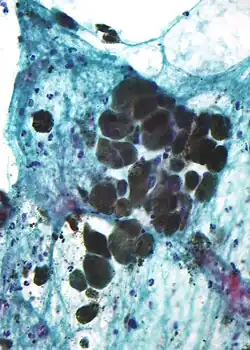

Micrografia do pigmento melanina (material granular refratário à luz — centro da imagem) em um melanoma pigmentado